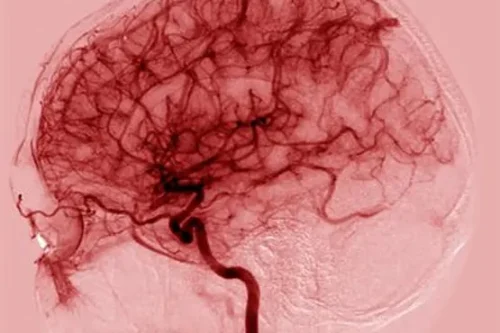

Brain mapping, also known as quantitative electroencephalography (qEEG), is a cutting-edge technology that analyzes brain waves. It helps uncover unique patterns that offer insights into cognitive functions, emotional well-being, and overall brain health. Denver residents seeking a deeper understanding of their mental processes can benefit greatly from this innovative approach.